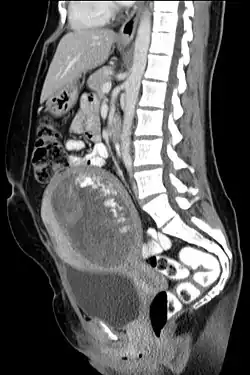

The diagnosis is strongly suggested by ultrasound (sonogram), but definitive diagnosis requires histopathological examination. On ultrasound, the mole resembles a bunch of grapes ("cluster of grapes" or "honeycombed uterus" or "snow-storm").[14] There is increased trophoblast proliferation and enlarging of the chorionic villi, and angiogenesis in the trophoblasts is impaired.[15]